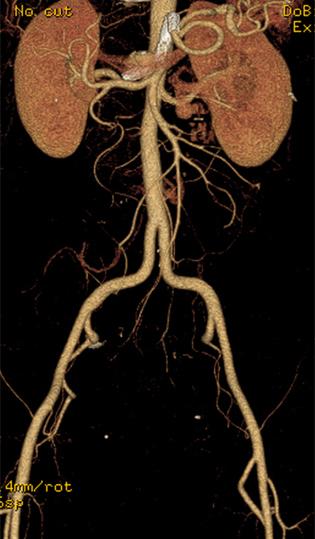

Permiteevaluarnosololosdiversosórganos delcuerpocomoeltejidocerebral,sino tambiénlosvasossanguíneos.Seutilizaen estudiosderutinaparaanalizarelcuello,cere‐bro,tóraxylosdiferentesórganosdelabdo‐men,asícomoloshuesos.Susoftwarepermi‐teprocesarreconstrucciones3Dcongráficos derealidadvirtualdeexcelentecalidad,que sondegranutilidadparaclínicosycirujanos. Conestatecnologíasereduceladosisde radiaciónenhastaun80%,estolohaceuna excelenteopciónenpacientespediátricosy adicionalmentesoportahasta205kgdepeso, muyútilenpacientesbariátricos.

Estáequipadoconunagrancantidadde aplicacionessofisticadasqueabarcan especialmenteestudioscardiovasculares:Se puedeevaluarelcorazón,analizarmediante angiotomografíacoronariasusarteriasyrea‐lizarprotocolosparapacientesaquienesse lesplanearealizarunreemplazovalvular.Tie‐neunaresoluciónespacialquebrindamejor definicióndeimagenenestudioscomo angiotomografíademiembrospélvicos, angiotomografíaaórtica,angiotomografía cerebral,angiotomografíadetroncossupra‐aórticos,loquepermitediagnosticaryplanifi‐carlosprocedimientosencasoscomoaneu‐rismas,estenosisoanomalíasvasculares. Cuentaconherramientasfuncionalescomo perfusióncerebralyesposiblerealizarestu‐dioscomotomografía,colonoscopíavirtual, enteroUrotomografía.